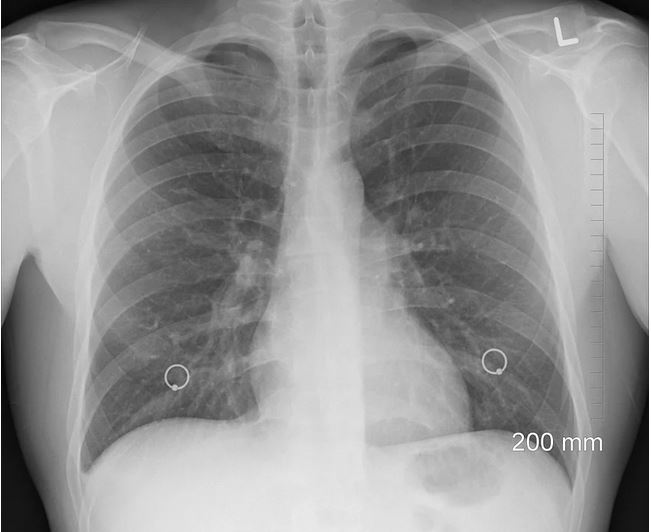

Long-Term Mask Use May Contribute to Advanced Stage Lung Cancer, Study Finds